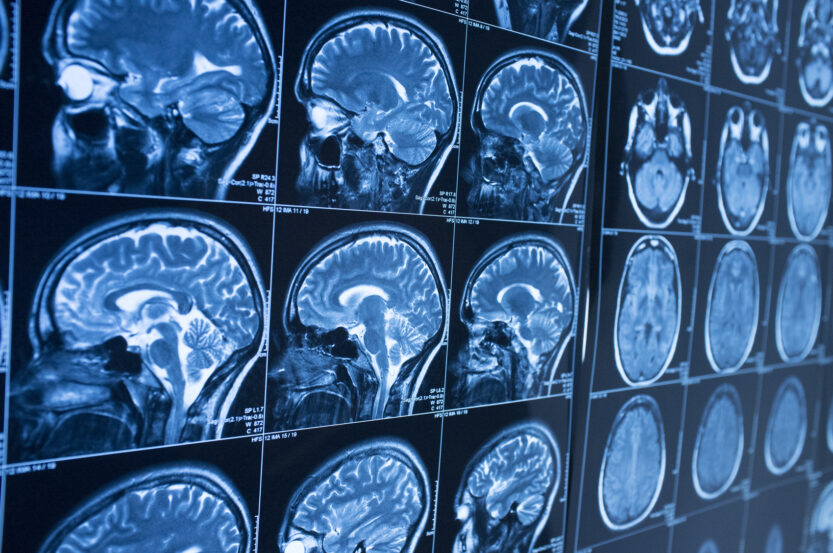

The pain and suffering caused by nerve damage are difficult to communicate. However, the plaintiff can objectively show that the nerve damage occurred. Nerve conduction tests can prove that certain nerves are impaired. The plaintiff’s injuries can also be shown to typically correspond with nerve damage.